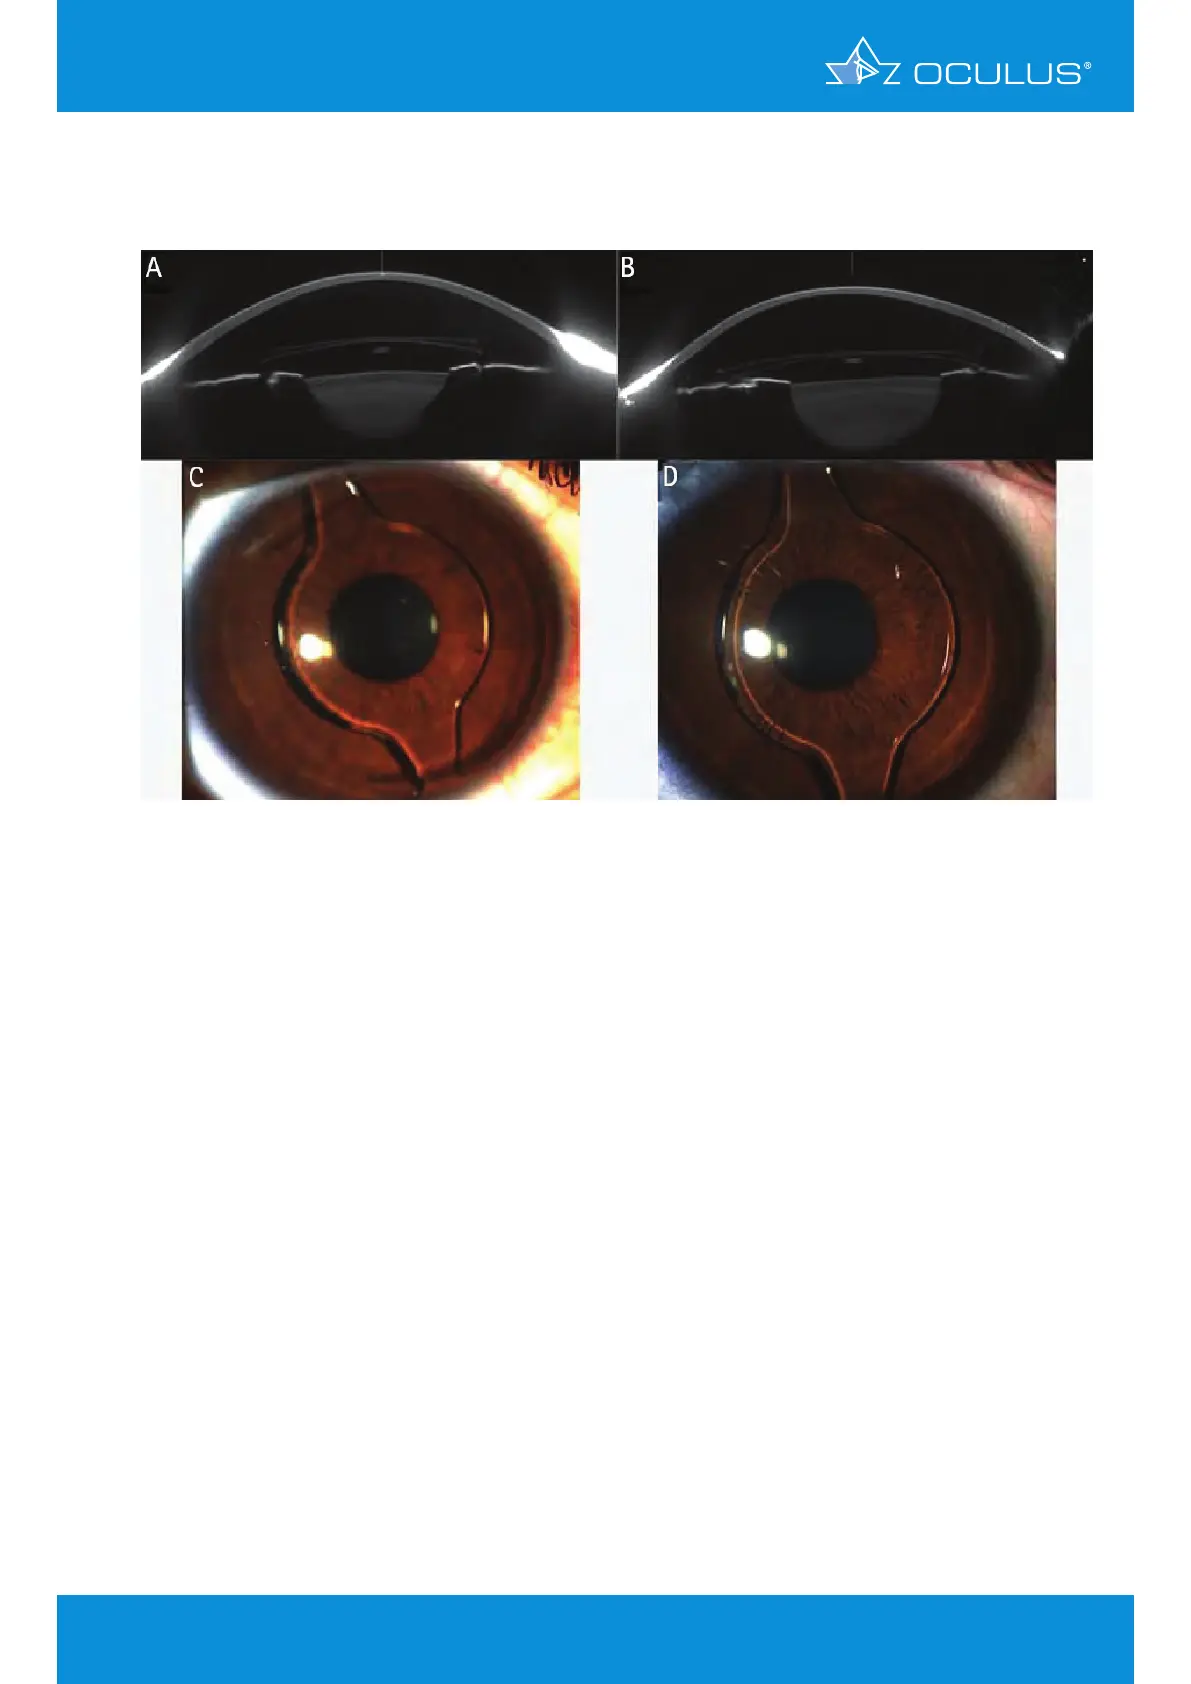

22 Phakic IOL implantation

Clinical case of post-LASIK ectasia treated by transepithelial crosslinking followed by phakic

intraocular lens implantation in both eyes.

Figure 186: Scheimpflug Image after transepithelial crosslinking in OD (A) and OS (B),

slit-lamp photograph showing pIOL implant in OD (C) and OS (D)